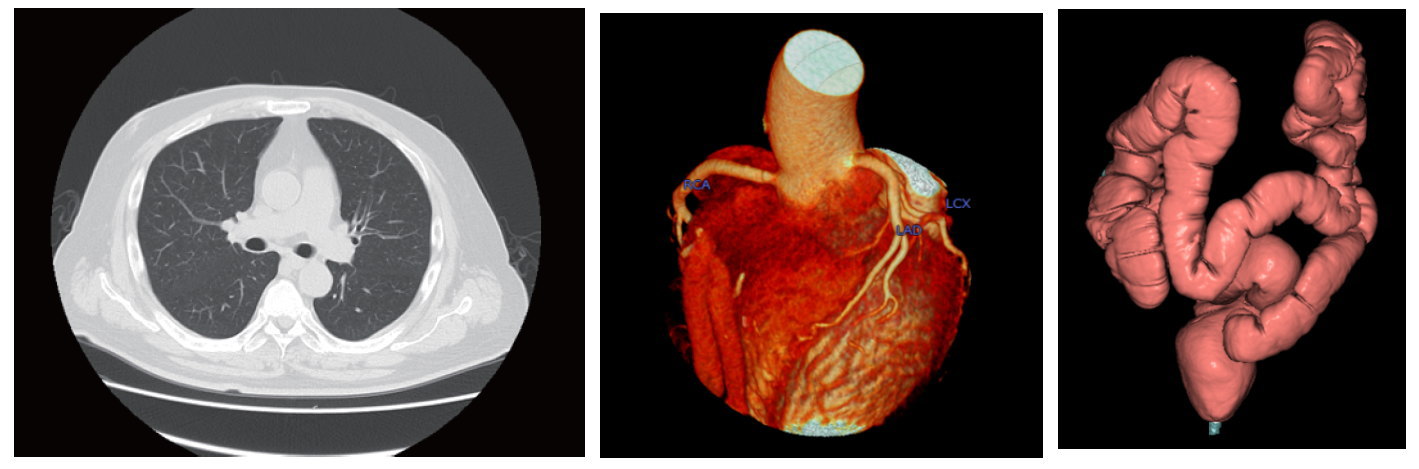

当院では、320列CT装置(キャノンメディカル製Aquilion One)を導入しています。

検出器が320 列並んでおり、広範囲を一度に短時間で撮影できます。

これにより、撮影時間を短くし、患者さんの放射線被ばくや、造影剤使用量を減らせます。

心臓(冠動脈)CT 検査や、大腸CT 検査も行っています。 - 詳しくはこちらから PDF